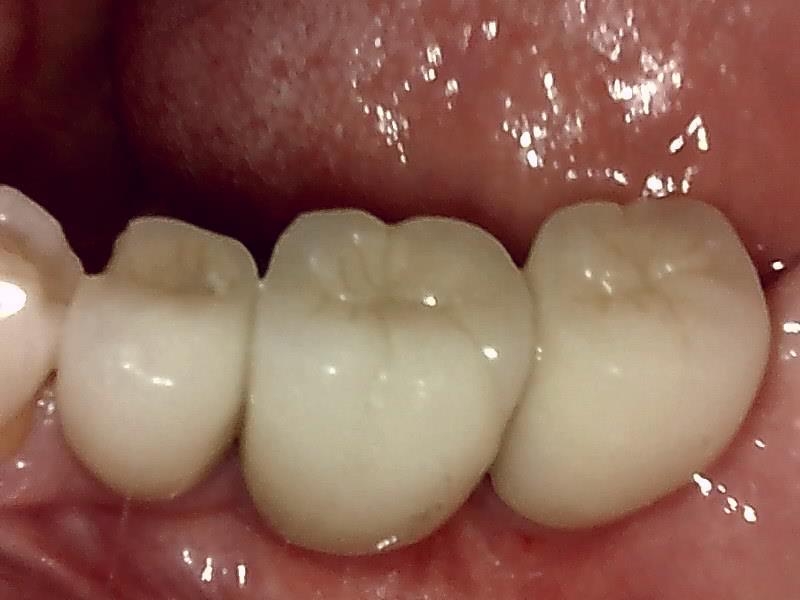

インプラントの上部構造 (左下)

(ジルコニアセラミッククラウン)

術後、とても経過良好です。